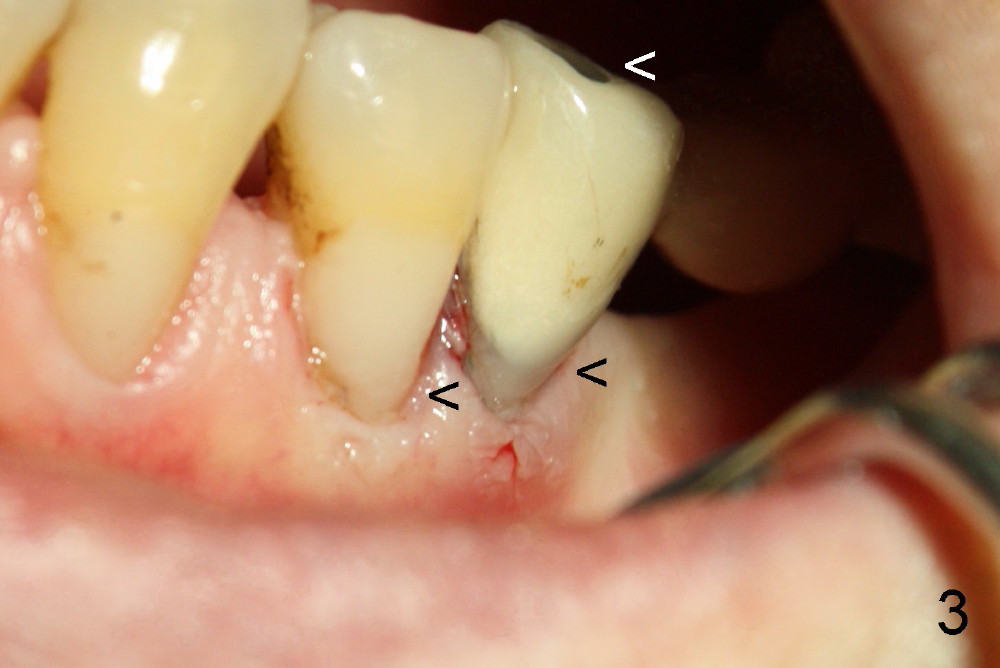

比较上文图一图二,我们可以发现第二前磨牙牙冠下面所谓裂纹(上文图二白箭头)似乎五年前也可以看见(上文图一)。当病人第二次回诊所,我们再次仔细检查发现那个牙齿(本文图一P2)的确有牙颈部缺损(黑箭头),仿佛牙髓暴露(白箭头)。当从牙冠牙合面开髓(其实这项手术很危险,容易穿髓),插入十号牙髓针(图二F),牙髓针的下部在牙颈部缺损暴露(^,不巧当时橡皮障掉下来)。第一前臼齿有一牙颈部树脂修复(C)以及继发性龋齿(<)。总之第二双尖牙牙髓炎很可能由于牙颈部缺损穿髓造成,根管治疗会解决疼痛问题,至于根管治疗后牙齿可能断裂是以后问题。